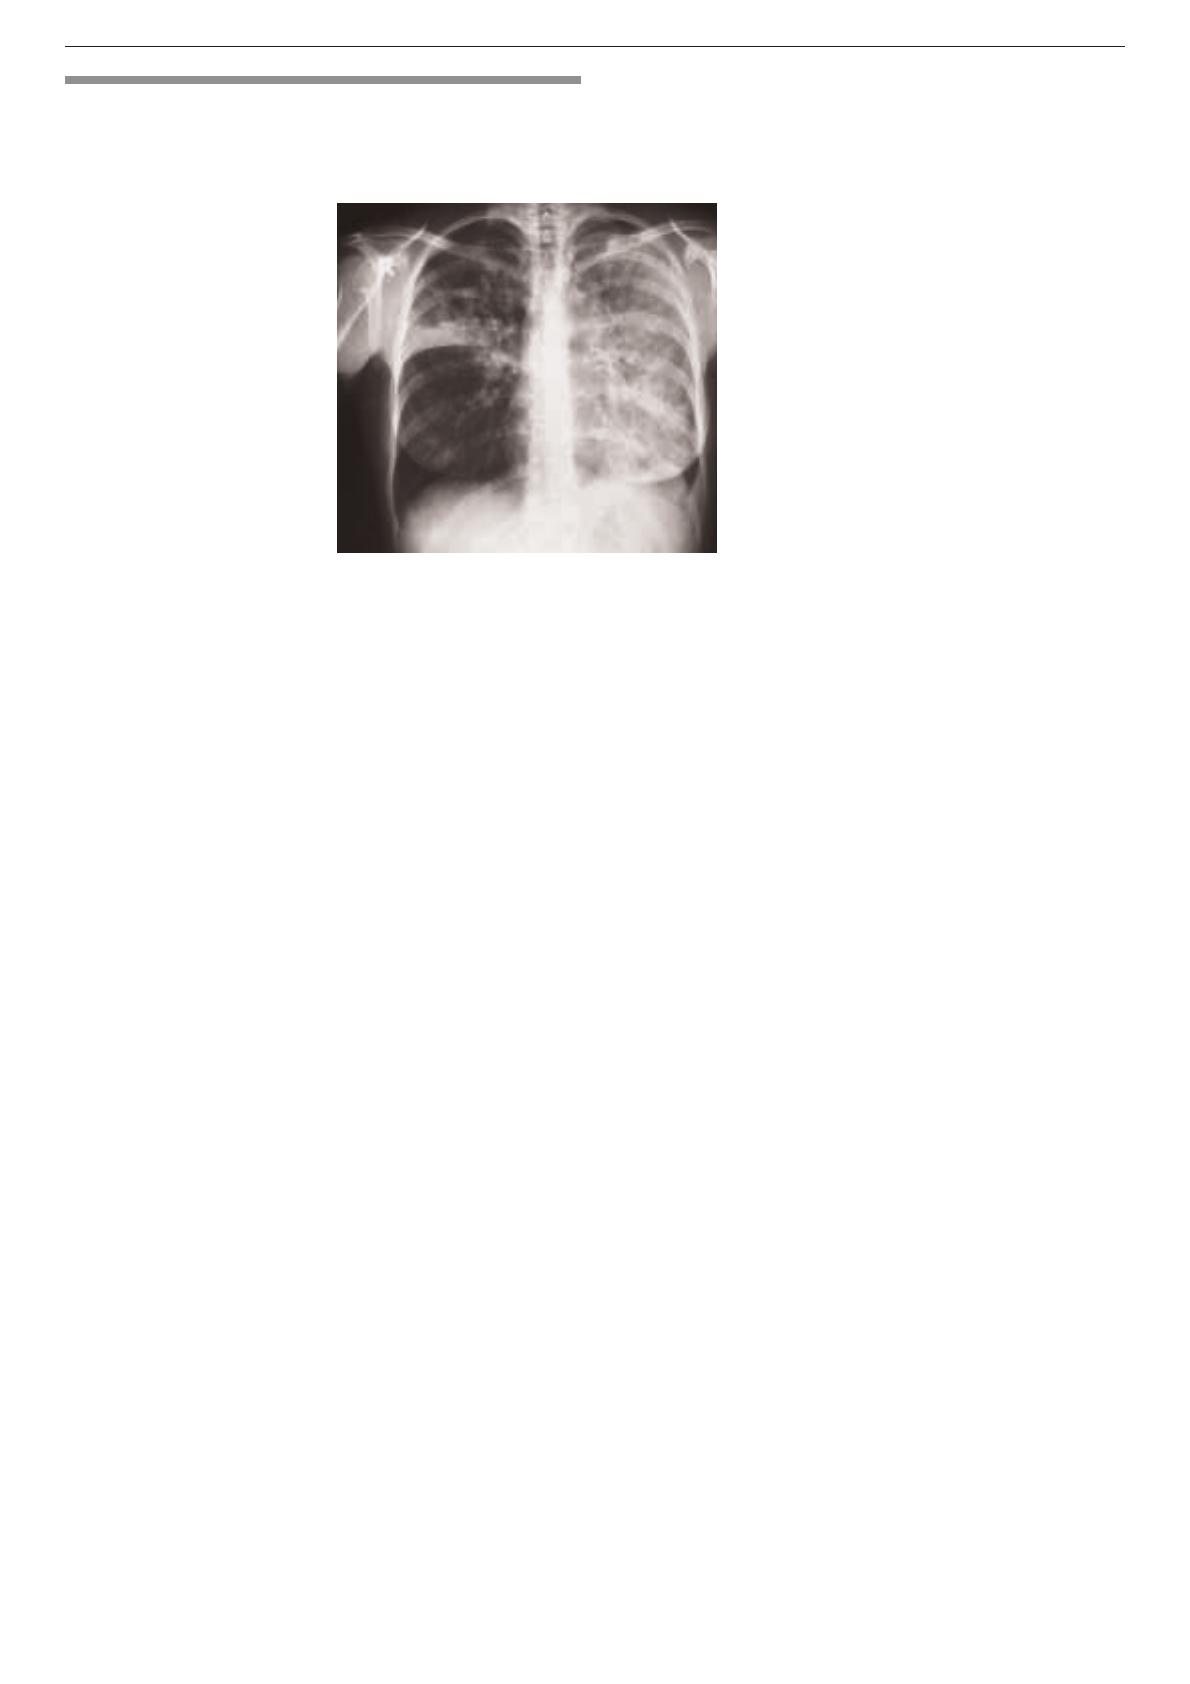

Figure 2.

Patiente ayant une «pneumonie»

subaiguë sans amélioration sous

antibiotiques. Formule sanguine

normale, mais 38% d’éosinophiles

au lavage bronchiolo-alvéolaire.

Amélioration rapide de cette

pneumonie à éosinophiles sous

stéroïdes.

CURRICULUM Forum Med Suisse No44 29 octobre 2003 1055